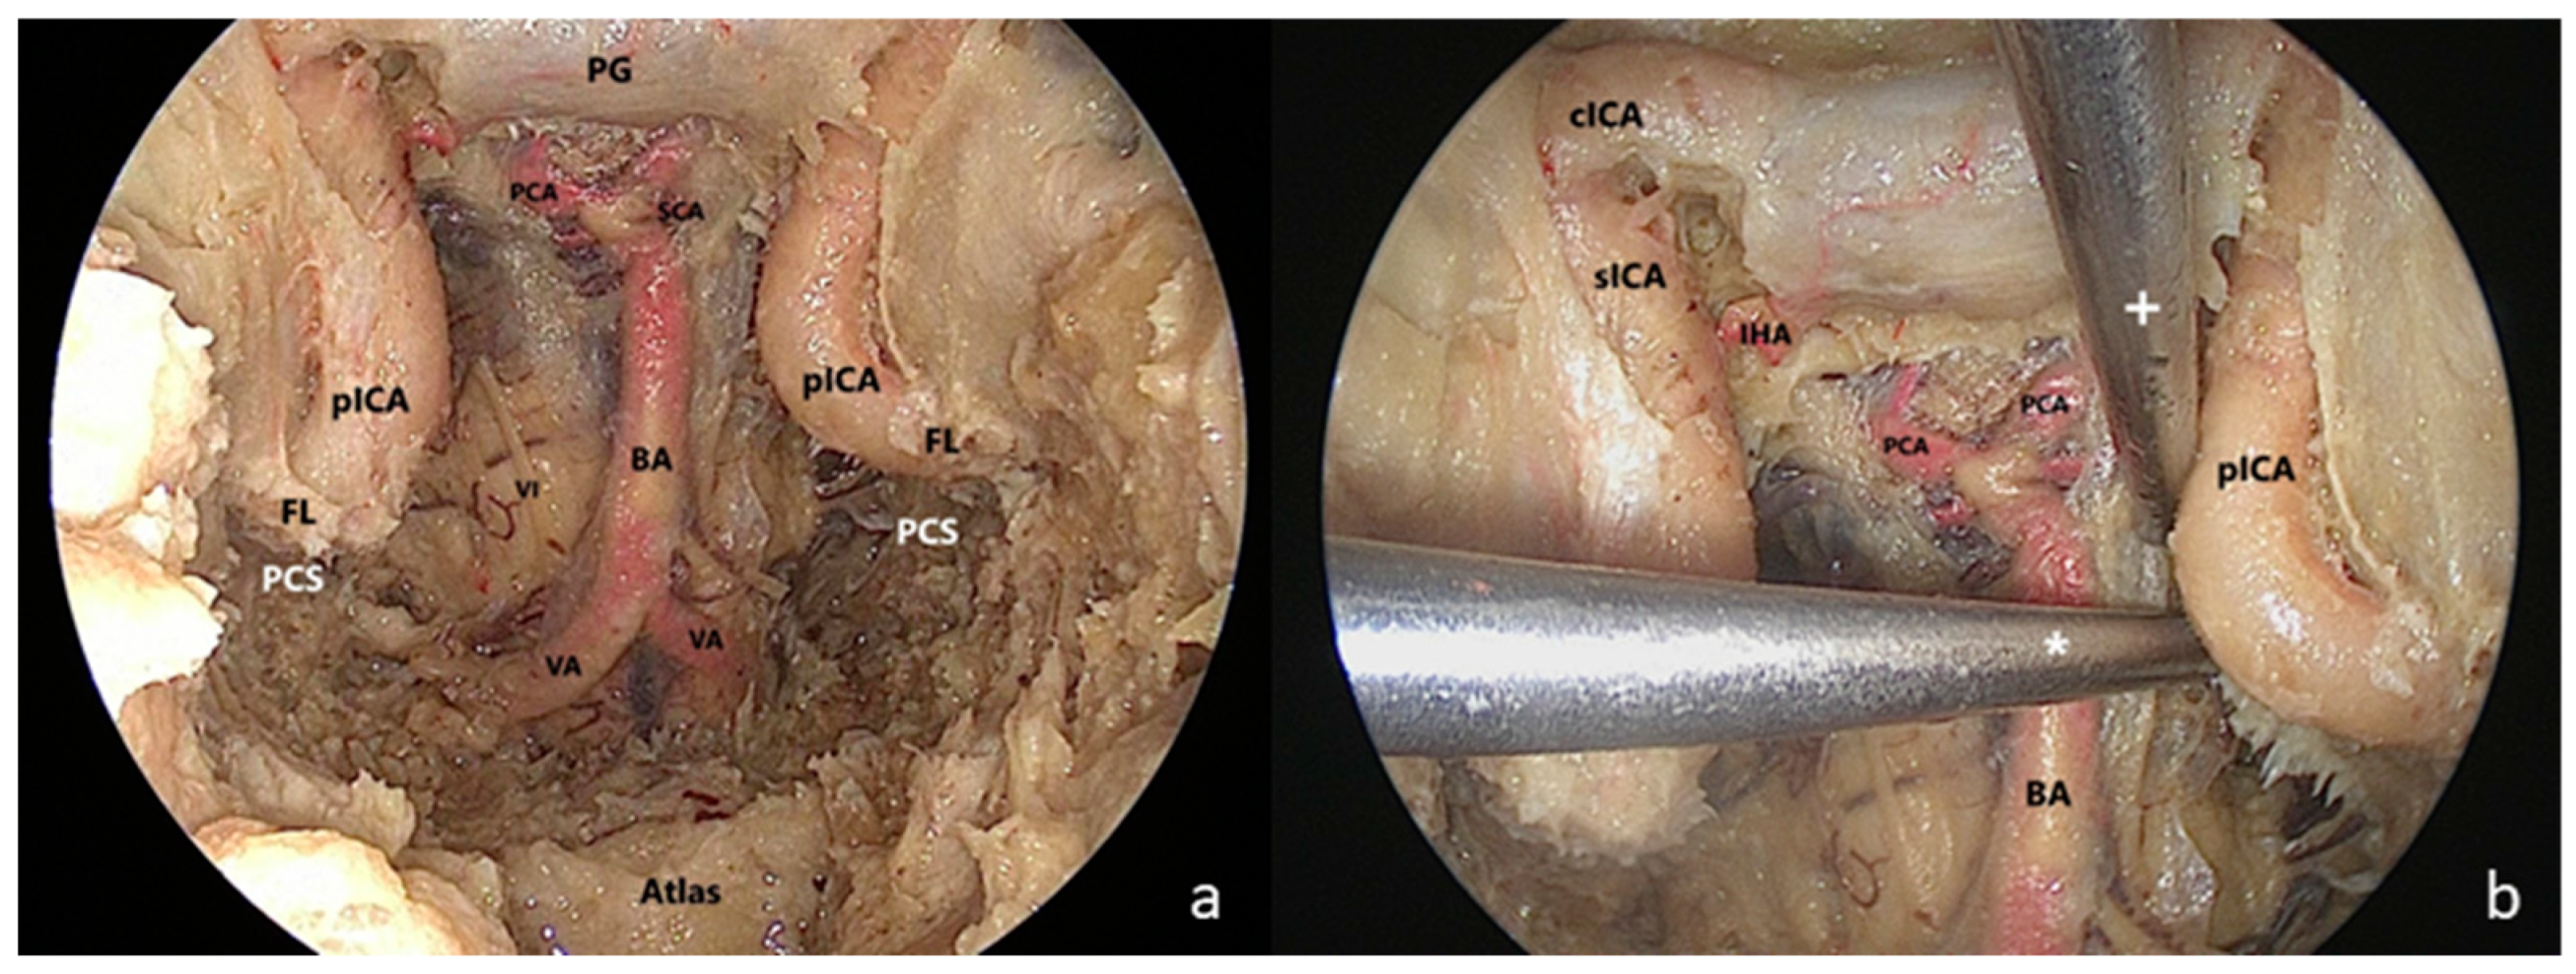

2.2. Surgical Technique

- The clival step

- The maxillary step

- The petrosal step

4.1. Surgical Anatomy Considerations